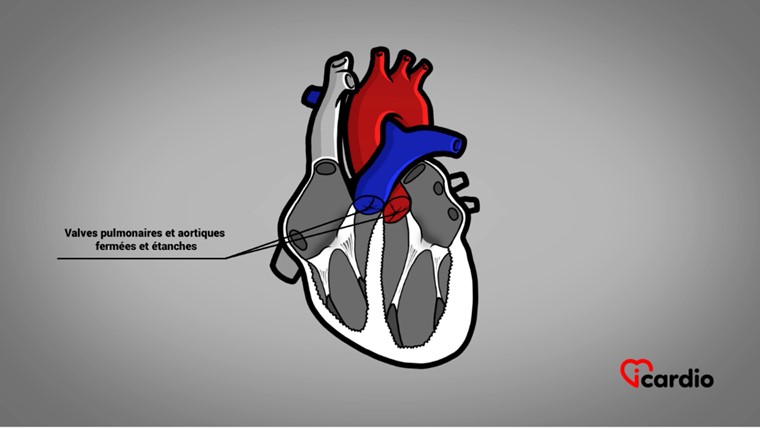

Les 4 valves du cœur

Le cœur possède 4 valves qui permettent d’assurer une circulation sanguine dans le bon sens… sans possibilité de retour vers l’arrière !

2 de ces valves cardiaques sont la valve pulmonaire et la valve aortiqueLa valvule aortique est située entre le ventricule gauche et l’aorte. C’est l’une des quatre valves du cœur. >>. Elles sont situées à la base des gros vaisseaux, soit à la sortie des ventriculesLes ventricules sont les 2 cavités inférieures du cœur. Ils sont plus musclés que les oreillettes; ils servent à propulser le sang pour assurer la circulation dans tout le corps. >>.

On les appelle valves tricuspides parce qu’elles sont formées de 3 cupules reliées à l’anneau. Elles séparent respectivement l’artère pulmonaire du ventricule droit et l’aorte du ventricule gauche.

Les cupules sont des genres de pochettes extrêmement souples qui se replient contre leur anneau à l’éjection du sangLe sang est composé de globules rouges, de globules blancs, de plaquettes et de plasma. Les globules rouges sont responsables du transport de l’oxygène et du dioxyde de carbone. Les globules blancs constituent notre système de défense >> par les ventriculesLes ventricules sont les 2 cavités inférieures du cœur. Ils sont plus musclés que les oreillettes; ils servent à propulser le sang pour assurer la circulation dans tout le corps. >>.

Après l’éjection, la colonne de sang tente un retour vers l’arrière en raison de la diminution de pression et de l’effet de succion causés par le relâchement des ventriculesLes ventricules sont les 2 cavités inférieures du cœur. Ils sont plus musclés que les oreillettes; ils servent à propulser le sang pour assurer la circulation dans tout le corps. >>. Cette tentative de recul fait rouvrir les cupules, bloquant le sangLe sang est composé de globules rouges, de globules blancs, de plaquettes et de plasma. Les globules rouges sont responsables du transport de l’oxygène et du dioxyde de carbone. Les globules blancs constituent notre système de défense >> et rendant la valve étanche.

Ainsi, la seule voie de sortie du sangLe sang est composé de globules rouges, de globules blancs, de plaquettes et de plasma. Les globules rouges sont responsables du transport de l’oxygène et du dioxyde de carbone. Les globules blancs constituent notre système de défense >> se fait à travers la valve pulmonaire, à droite, et la valve aortiqueLa valvule aortique est située entre le ventricule gauche et l’aorte. C’est l’une des quatre valves du cœur. >>, à gauche.